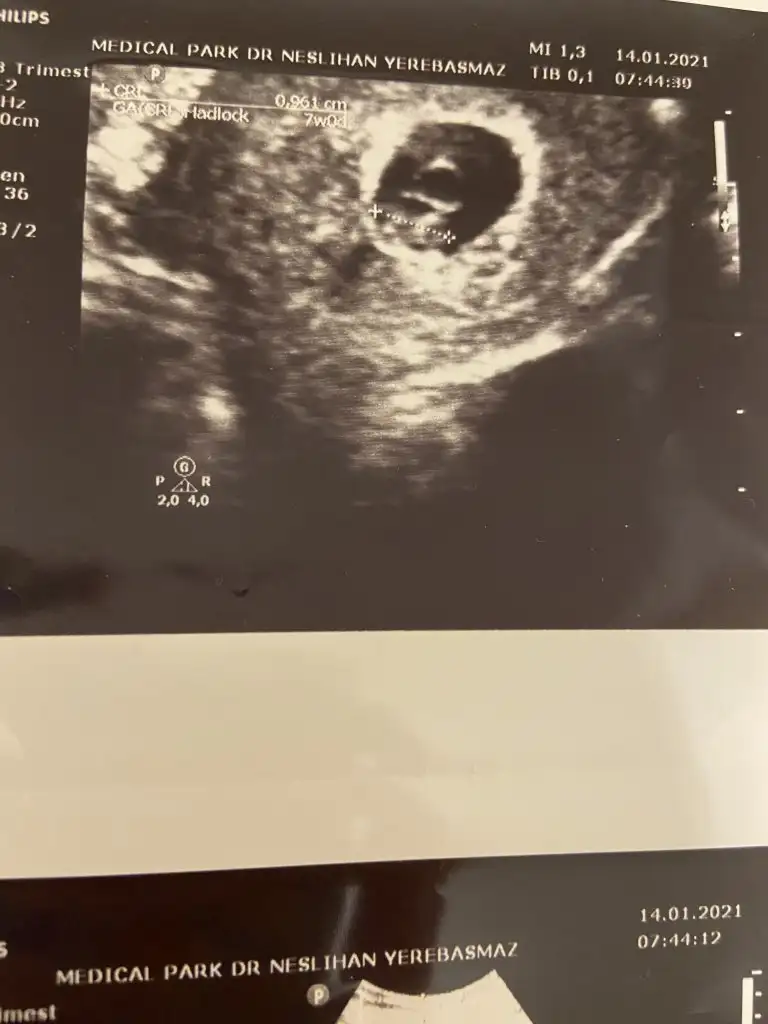

Evet yalan uYdurma olabilir bizde girgirina yapiyoruz doktor degilimBence bu hepsini yalanlıyor 6 haftalık kız 7 haftalık erkek gibi duruyor. Demekki bebeğin yeri surekli değişiyor teori yalan

Sanırım kız gibi geldi banaMerhaba benim bebişin cinsiyetinide tahmin edebilir misiniz?Üzerinde haftalar yazıyor . 6 haftalık vajinadan 7 haftalık karından simdiden teşekkür ederim